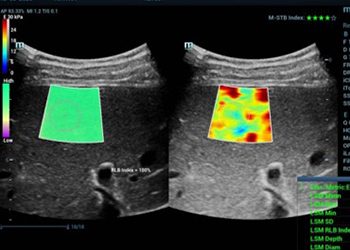

elastography

Elastography examination assesses the stiffness of human body tissue.